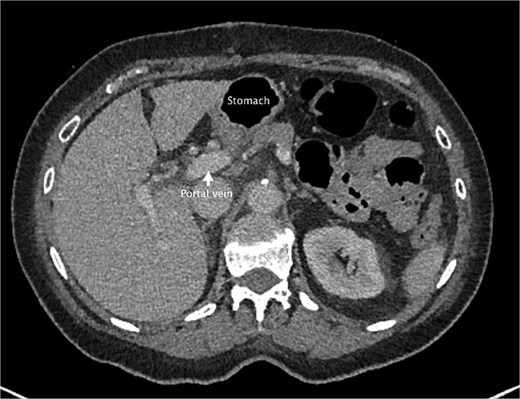

An axial slice from the pre-operative CT abdomen pelvis in portal venous phase. There is an arrow pointing to narrowed appearance of portal vein. Also labeled are the herniated colon anteriorly and the stomach to the left of the herniated colon.

She had a computed tomography (CT) abdomen and pelvis in the emergency department, which was initially reported as mesenteric panniculitis. She had an initial lactate of 3.3 mmol/l (reference range < 2.0), other blood tests, including white cell count and hemoglobin level, were normal. C-reactive protein was also normal. She was referred to the surgical team in the morning to determine a follow-up plan as her pain had improved and she was planned to be discharged home. On review by the surgical team, she was clinically well, her abdomen was soft and not tender on examination. However, on review of the CT images, there appeared to be a dilated segment of colon in the right upper quadrant, and on further analysis, it appeared to be a Foramen of Winslow hernia containing colon. There was also an area that appeared to demonstrate a potential filling defect in the portal vein along with periportal oedema. This raised the concern of a potential thrombus versus vascular congestion (Figs 1 and 2).